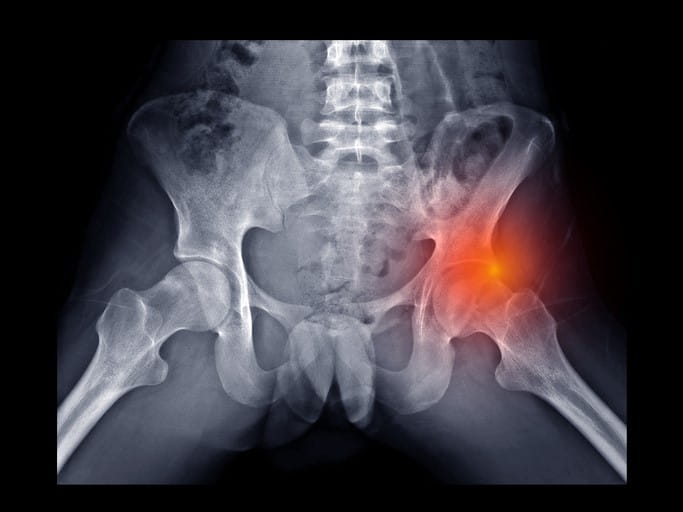

How Do You Diagnose FAI?

To diagnose FAI, your doctor will ask about your medical history and do a physical exam. They'll gently raise your knee toward your chest and rotate it inward. If you have any discomfort or pain during this maneuver, it may indicate a hip impingement.

Tests to diagnose FAI

To confirm the diagnosis, your doctor may request imaging tests to assess for FAI and any potential bone abnormalities. These scans will also provide a clear view of any joint damage.

Tests may include: